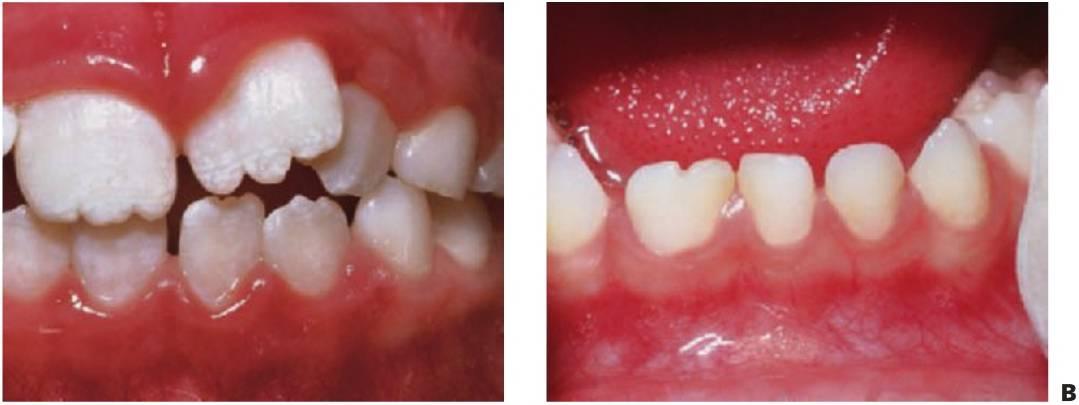

Hipodoncia, oligodoncia y anodoncia son los términos que designan los diferentes grados de progresión de la ausencia de dientes, si bien el término hipodoncia es el más utilizado debido a que se refiere a un número indeterminado de dientes ausentes (fig. 9.1 A). La oligodoncia designa la ausencia de seis dientes o más, y la anodoncia la ausencia completa de dientes. Todos estos casos se producen debido a un fallo en el desarrollo. El término «dientes ausentes congénitamente» no puede aplicarse a la dentición permanente, ya que estos dientes comienzan su desarrollo después del nacimiento, y tampoco a la dentición temporal ya que esa ausencia dental no puede determinarse de forma clínica en el momento de nacer; asimismo, el término «anodoncia parcial» carece de sentido. Sucede con frecuencia que los grados de hipodoncia aparezcan de manera esporádica o bien tengan un componente hereditario. Cuando a un individuo le faltan muchos dientes se debe estudiar a otros miembros de la familia afectados.

- Varios dientes ausentes (fig. 9.1 B).

Los dientes son pequeños y cónicos y a menudo presentan un gran diastema anterior (fig. 9.3). Sus manifestaciones pueden limitarse a un solo diente ausente o a un incisivo lateral en clavija (v. hipótesis de Lyon, más adelante) y las mujeres heterocigóticas suelen ser diagnosticadas gracias a este tipo de dentición.

Los dientes supernumerarios surgen como resultado de una geminación de la lámina dental que se produce de forma esporádica o se heredan, como sucede con la displasia cleidocraneal (fig. 9.8).

La forma de los dientes puede recordar a la forma de las piezas normales (diente suplementario), es decir, incisiforme, caniniforme o molariforme; de no ser así, sería cónico o tuberculado.

Habitualmente se presenta como consecuencia del fallo en la erupción de uno o más dientes permanentes y en general presenta formas cónicas o tuberculadas.

- Erupción fallida o ectópica de un diente permanente (fig. 9.8B).

- A menudo erupcionan dientes cónicos que se pueden extraer con mucha facilidad (fig. 9.8A).